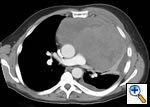

Any anterior mediastinal mass (Figures 1, 2) must be considered suspect for germ cell tumor, especially in a young male. Errors in diagnosis are not uncommon and can result in mismanagement of a potentially curable patient. All patients with an anterior mediastinal mass should have alpha-fetoprotein (AFP), β-human chorionic gonadotropin (β-HCG), and lactate dehydrogenase (LDH) levels drawn at the outset. The different types of germ cell histologies are shown in Figure 3.